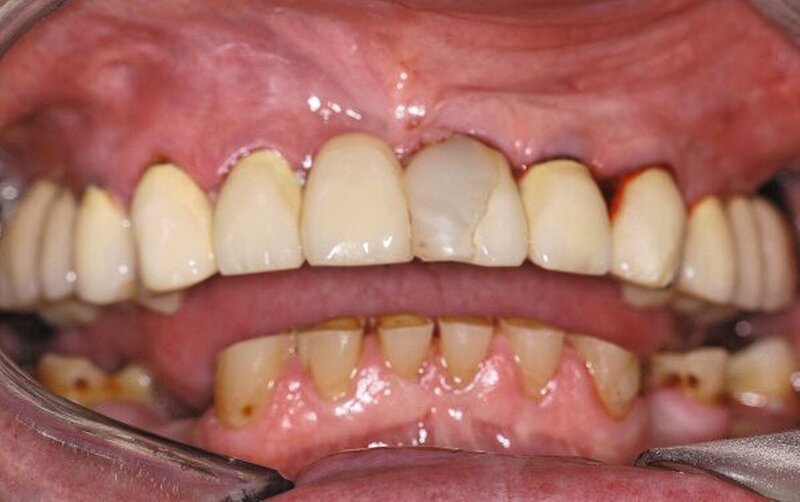

Im Rahmen der intraoralen Befunderhebung wurde festgestellt, dass die Gingiva insgesamt gerötet und ödematös war. Die Messung der Taschentiefe ergab einen durchschnittlichen Wert von fünf mm. Der ermittelte PSI (in Bezug auf die Sechstanten) ergab die Werte 4, 2, 4, 3, 2, 2. Pusaustritt konnte in regio 17 und in regio 27 festgestellt werden, so dass der Erhalt dieser Zähne fraglich war. Im Oberkiefer lag ein prothetisch versorgtes Lückengebiss der Kennedy-Klasse III2 vor. Die Zähne 18, 16, 15, 11, 25, 26 und 28 fehlten. Die prothetische Versorgung bestand aus einer Brücke 17 bis 14 zum Ersatz von 16 und 15, einer Brücke 13 bis 23 zum Ersatz von 11 und einer Brücke 24 bis 27 zum Ersatz von 25 und 26. Sämtliche Brückenanker wiesen Randundichtigkeiten und Sekundärkariesbildung auf. An 21 konnte eine großflächige Keramikabplatzung festgestellt werden. 17 und 27 reagierten im Perkussionstest stark positiv. Im Rahmen einer Sensibilitätsprüfung mittels CO2-Schnee reagierten die Zähne 17, 22 und 27 negativ. Im Unterkiefer lag ein Gebiss der Kennedy-Klasse II3 vor. Die Zähne 38, 36, 34, 44, 45, 47 und 48 fehlten. Die Zähne 37, 42, 46 waren mit Füllungen versorgt, die erhebliche Undichtigkeiten aufwiesen. 46 reagierte im Kältetest negativ. Alle Unterkieferzähne wiesen starke Attritionen auf. Diese Zähne 33 bis 43 sowie 37 und 35 reagierten im Kältetest stark schmerzhaft (Abbildungen 4, 5).